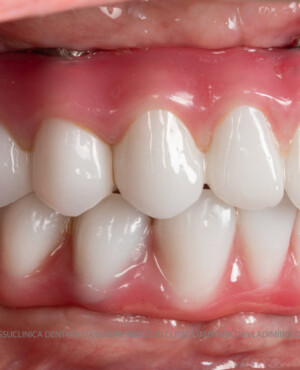

- Posibilitatea realizării unei proteze cu 12-14 dinți, oferind un aspect estetic natural și funcționalitate optimă.

Pentru pacienții cu edentație extinsă sau dinți nefuncționali, metoda All-on-6 oferă o alternativă modernă și eficientă la proteza mobilă, asigurând o restaurare fixă, stabilă și estetică a danturii. Datorită distribuirii optime a implanturilor și a tehnologiei avansate implicate, această soluție îmbunătățește considerabil calitatea vieții, confortul și funcționalitatea orală. Succesul tratamentului depinde de o planificare riguroasă, de utilizarea componentelor de calitate și de competența echipei medicale, ceea ce face ca alegerea unei clinici specializate să fie esențială pentru obținerea unor rezultate durabile și sigure.